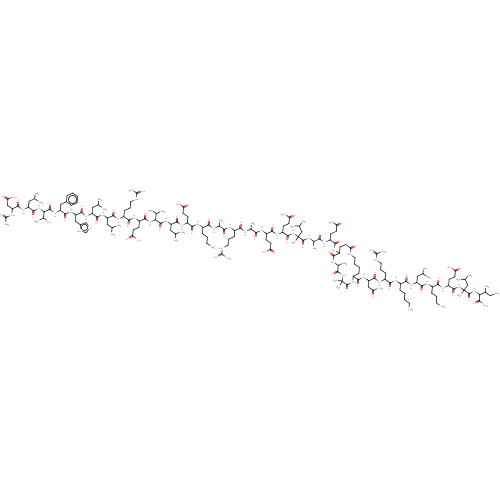

TargetCorticotropin-releasing factor receptor 1(Homo sapiens (Human))

Dupont Pharmaceuticals

Curated by ChEMBL

Dupont Pharmaceuticals

Curated by ChEMBL

Affinity DataEC50: 3.5nMAssay Description:Activity of peptidic agonists on corticotropin releasing factor receptor receptor using agonist-stimulated adenylate cyclase assayMore data for this Ligand-Target Pair